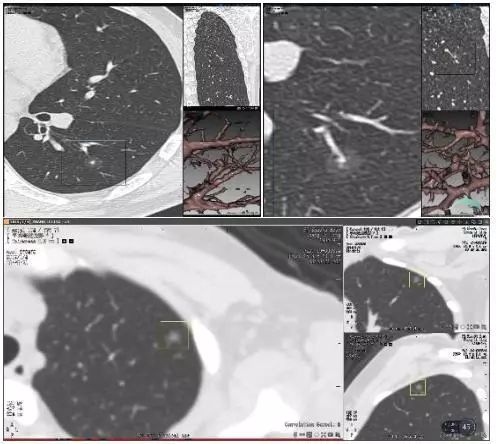

实性肺结节(solid nodule),间质血管都看不见(左上图),亚实性肺结节(subsolid nodule)包括纯磨玻璃结节(pure ground-class nodule,pGGN)(左下图),还有混杂性结节(mixed ground-glass nodule,mGGN),也称部分实性结节(part solid nodule),表现为间质样改变,中间实性,周围是磨玻璃样。